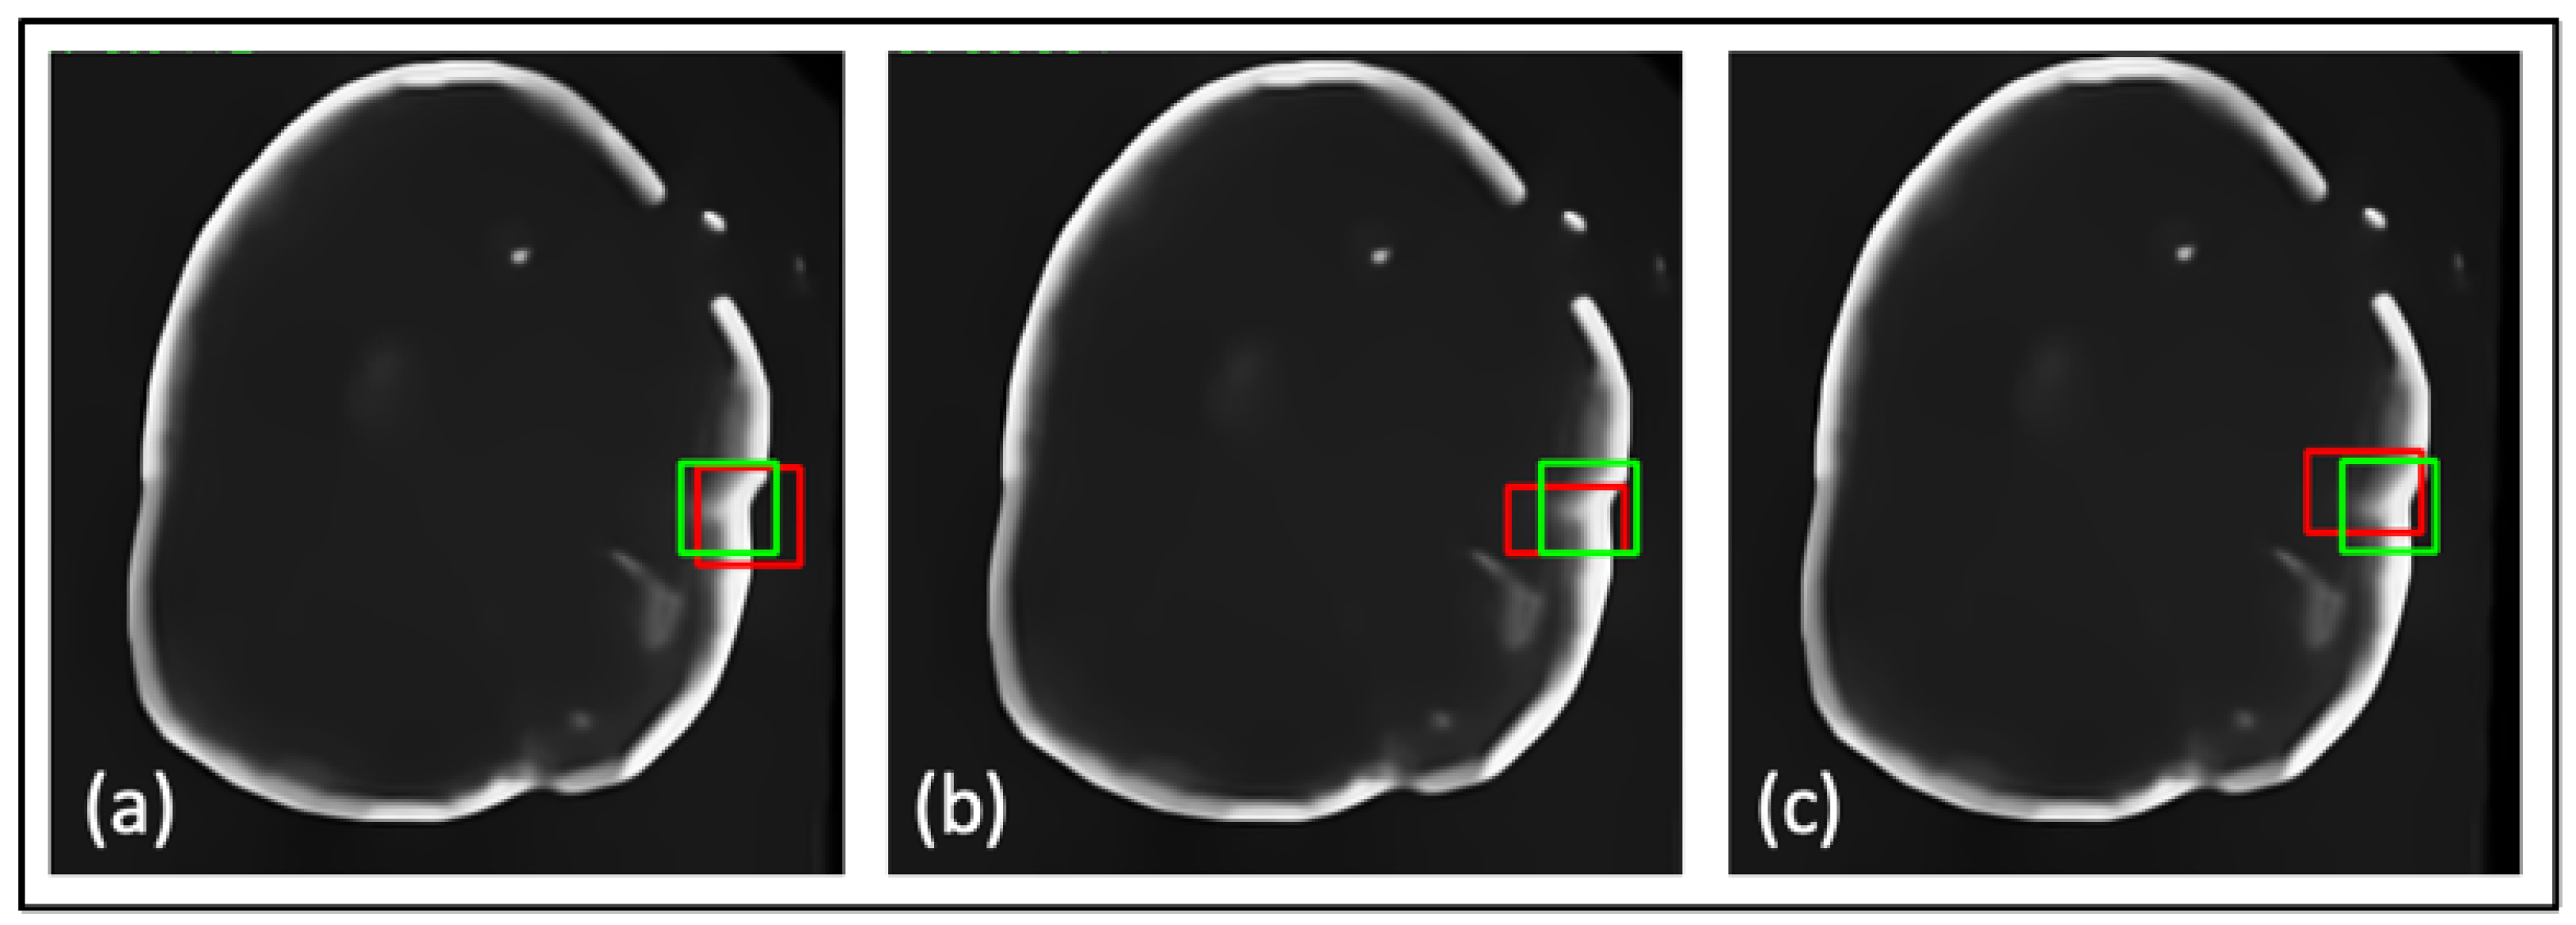

- A novel TED framework is developed, focusing on detecting relevant lesions in noisy OCT images of different organs.

- In TED, the transformer is adapted to take in images and slide across Regions of Interest (ROIs) provided by AGs. This design aims to adaptively deal with different types of noise artifacts and thus effectively detect a variety of anomalies including tooth decay and numerous lesions across two modalities.

- A new loss function is proposed along with TED, which combines a sliding box, Intersection Over Union (IOU), and Mean Squared Error (MSE). It compares the IOU and MSE between the predicted and real bounding boxes to evaluate the regions of focus chosen by the AGs.